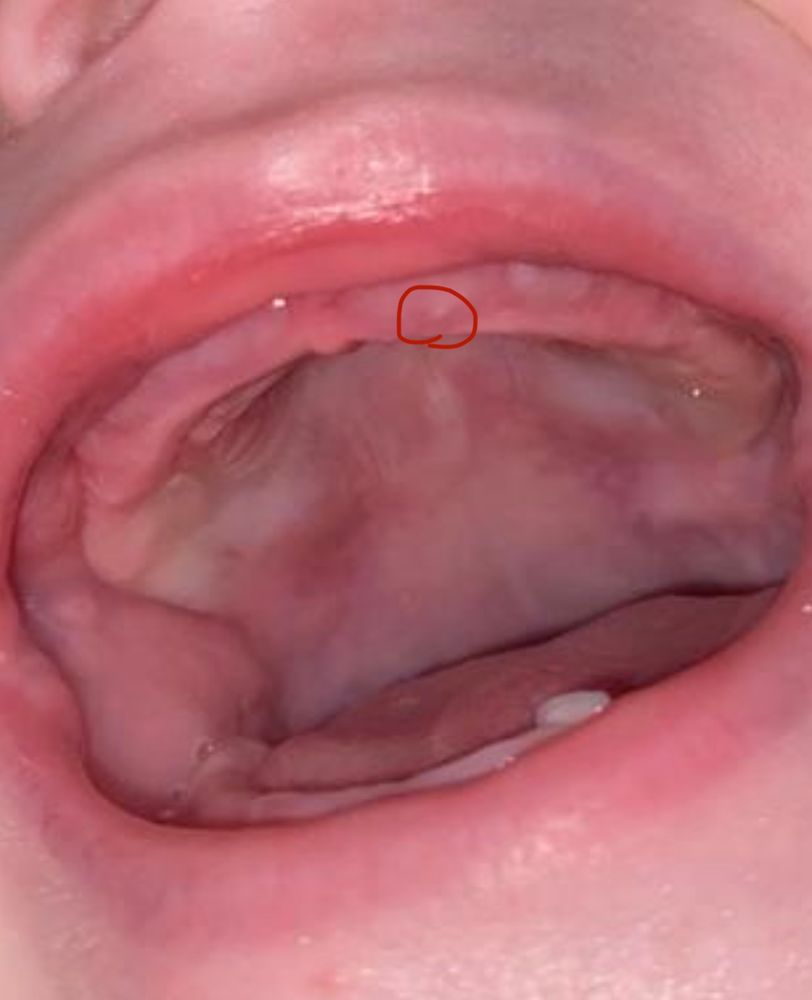

эти белые точки вверху-зубы? Нижний по-другому резался . Сын уже неделю беспокойный, сон ужасный, через каждые 40 - 50 минут плач , пока на ручки не возьмешь и не укачаешь -не успокаивается …

и вроде внизу что/то наклевывается, не пойму ..